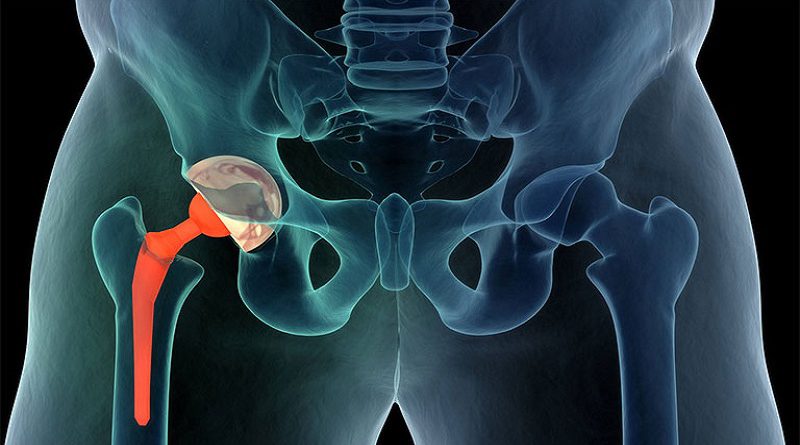

Phục hồi chức năng sau phẫu thuật chấn thương chỉnh hình - cột sống